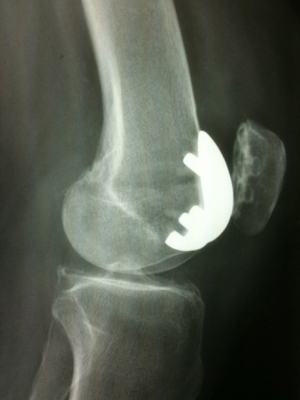

2 - LA CHIRURGIE PROTHETIQUE DU GENOU La chirurgie prothétique est une operation du genou qui a considérablement changé la vie des patients atteints de gonarthrose. Lorsque toutes les techniques médicales ont été épuisées (antalgiques, anti-inflammatoires, infiltrations de corticoïdes ou d’acide hyaluronique, rééducation et physiothérapie, etc.), le traitement chirurgical par remplacement total ou partiel de l’articulation s’impose. La proths, la technique, les matériaux, la conception de ces prothèses ont considérablement évolué en 30 ans. Actuellement, la tendance est d’utiliser du chrome-cobalt pour la pièce fémorale (proche de l’acier inox), du titane pour la pièce tibiale et du polyéthylene pour la pièce intermédiaire fémoro-tibiale et la pièce rotulienne. La prothese du genou peut être cimentée ou non. La pièce intermédiaire peut être fixe ou mobile rotatoire (plateau fixe ou mobile). Les ligaments croisés peuvent être ou non conservés. La prothese du genou peut être totale, remplaçant les 3 compartiments articulaires du genou (fémoro-tibial intèrne, fémoro-tibial externe et fémoro-patellaire) ou partielle (uni-compartimentaire interne, externe ou fémoro-patellaire) Il se pose actuellement environ 300 000 prothèses du genou aux Etats Unis et en Europe. En France, environ 50 000 prothèses implantées chaque année.

Pour ma part, j’utilise dans les prothèses totales un implant cimenté en tibial, un implant cimenté ou non en fémoral en fonction de la tenue primaire sur l’os, une pièce polyéthylène mobile rotatoire et une non conservation des ligaments croisés. La rotule n’est prothèsée que dans 10 % des cas, sinon je pratique une simple dénervation et une excision des ostéophytes périphériques. Pour les prothèses unicompartimentaires en cas d’arthrose localisée, j’utilise des implants cimentés à plateau fixe. La durée d'intervention de cette operation du genou est variable mais en moyenne elle dure une heure. LES DIFFERENTS TYPES DE PROTHESE DU GENOU Elles sont au nombre de trois : LA PROTHESE DU GENOU TOTALE(PTG) La PTG est donc utilisée lorsque la gonarthrose est complète, touchant au moins 2 des 3 compartiments du genou. Elle permet donc de reconstruire totalement l’articulation du genou en restaurant l’axe anatomique (corrige le varus ou le valgus), en redonnant une mobilité articulaire complète, en redonnant une stabilité au genou et surtout en faisant disparaître totalement les douleurs pour une durée importante (15 à 20 ans). La rotule ne doit être prothésée que lorsque son cartilage est totalement détruit, sinon il faut se contenter de réaliser une patelloplastie ou une patellectomie partielle en retirant tous les ostéophytes périphériques et en dénervant tout autour de la rotule en utilisant le bistouri électrique La PTG permet la reprise d’une marche normale sans douleur ni boiterie. | |

LA PROTHESE DU GENOU UNICOMPARTIMENTAIRE INTERNE OU EXTERNE (PUC) La PUC est donc implantée lorsque l’arthrose est limitée soit au compartiment interne soit au compartiment externe. Elle nécessite donc une très bonne évaluation des lésions et que l’on soit assuré du bon état des autres compartiments qui ne seront pas prothésés. | |

LA PROTHESE DU GENOU FEMOROPATELLAIRE ( PFP) Ce type de prothese du genou unicompartimentaire est implantée lorsque l’arthrose touche essentiellement le compartiment fémoro-patellaire, c’est à dire pour l’usure cartilagineuse de la rotule et ou de la trochlée; Elle est souvent associée à un geste de recentrage rotulien (section de l’aileron externe ou transposition interne de la tubérosité tibiale antérieure). Dans ce cas, la rotule est toujours remplacée par un médaillon rotulien cimenté. | |

LA TECHNIQUE CHIRURGICALE Pour tous les types de prothese du genou, la technique est similaire : L’anesthésie est soit générale, soit locorégionnale (rachi anesthésie). Le membre inferieur opéré est préalablement dépilé et préparé stérilement. Un garrot pneumatique est utilisé chaque fois que cela est possible pour éviter tout saignement per-opératoire. L’incision est soit antérieure, soit interne, en fonction du type de prothese du genou à implanter. La première étape consiste à ouvrir l’articulation et faire un bilan lésionnel. Ensuite, l’étape de nettoyage intervient. Les coupes osseuses se font avec un matériel ancillaire spécifique, sorte de « mécano », propre à chaque type de prothese du genou et à chaque laboratoire fabricant. Il existe bien sûr de nombreuses tailles ainsi que des implants droit et gauche. Actuellement certains laboratoires fournissent des modèles homme ou femme. Apres avoir choisi la taille, préparé les coupes osseuses fémorale, tibiale, trochléenne ou rotulienne, excisé tous les tissus usés (ménisques, ligaments croisés, synoviale etc.), une prothèse d’essai est provisoirement implantée et testée. Cette prothese du genou d’essai permet de tester le genou dans sa mobilité, sa stabilité, son axe anatomique et mécanique. Une fois vérifiée, la prothèse d’essai est retirée, le genou est lavé puis séché et la prothèse définitive est implantée, cimentée ou non en fonction des habitudes du chirurgien et de sa tenue primaire sur l’os. Le genou est toujours retesté avec sa prothese du genou définitive. La fermeture se fait le plus souvent après avoir mis un ou plusieurs drains intra articulaires qui seront laissés quelques jours et qui serviront à évacuer le saignement post opératoire. Une radio de contrôle est nécessaire juste après l’intervention pour s’assurer de la bonne position de la prothese du genou. Le cliché se fait en salle de réveil le plus souvent. | |